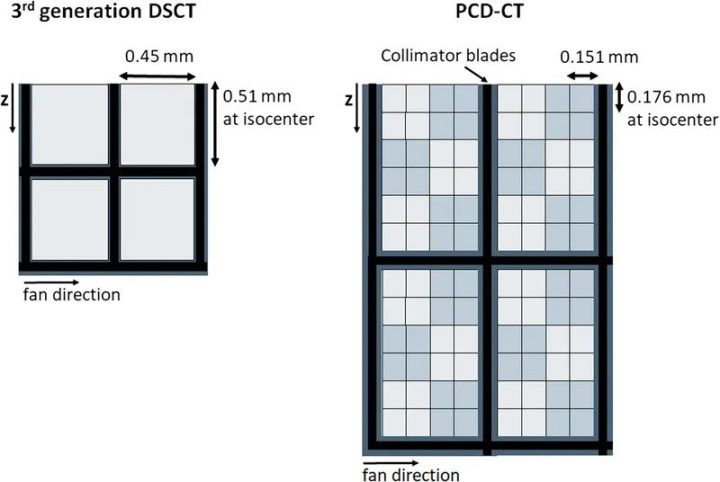

图4显示了市售PCD-CT与第三代DSCT的探测器结构对比。探测器像素大小为0.275×0.322mm2(等中心为0.151×0.176mm2)。每组4×6探测器像素通过一个二维准直器网格与相邻组隔开,以减少散射辐射。使用这种探测器和0.4×0.4mm2的焦点,可以实现超过40 lp/cm的分辨率,相当于0.125mm,见图5;这大约是EID-CT系统分辨率的两倍。在CT中,空间分辨率的提高总是伴随着图像噪声的增加或辐射剂量的相应增加;CT的这一基本规律也适用于PCD-CT。因此,必须采用基于迭代或深度学习的精细降噪技术。

图4 带有闪烁体探测器(左)和商用PCD-DSCT(右)的第三代DSCT的探测器结构示意图。从上往下看,z方向是病人的纵向。粗黑线示意性地表示用于抑制散射辐射的准直器网格。在超高分辨率模式下,PCD的探测器像素单独读出。在标准扫描模式下,2×2像素合并为一个宏像素–用浅灰色和深灰色方格表示。